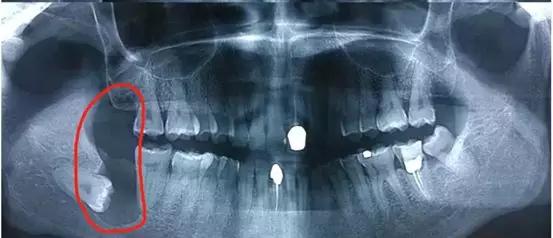

智齿萌发空间不足,常常会倒在第二磨牙上,因而造成第二磨牙清洁不易。智齿躺的时间一长,就会把旁边的邻牙都顶坏了,然后两颗都同归于尽。

这就是个玉石俱焚的案例。本来第一磨牙就缺失,智齿把第二磨牙也给顶牺牲了,种牙是在所难免了。